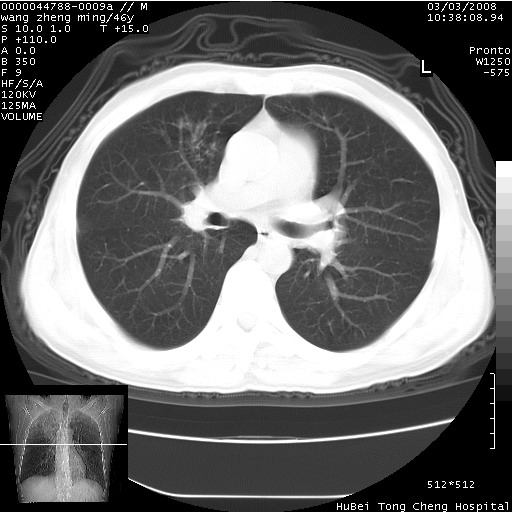

以下是引用卜一在2008-3-22 1:37:00的发言:[br]右肺实质性肿块,边缘不整,明显见毛刺征 分叶征及胸膜凹陷征,右上叶支气管明显变窄,远端散在的片状 斑片状实变影。另:左肺门较大肿块,支气管受累 变窄,远侧见阻塞性肺炎。纵隔内见肿大淋巴结。多考虑:右肺周围性肺癌伴左肺门 纵隔淋巴结转移!